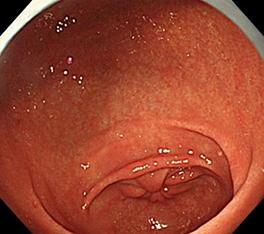

白色粘液⇒ボノプラザンの内服による粘液

前庭部、胃体部に萎縮の所見はなく、胃角でRACを認めることから、ピロリ未感染を疑うが、体部、穹隆部に存在する粘液が、ピロリ現感染の所見である白濁粘液ではないかと迷ってしまう。しかし、この症例の粘液は、白濁粘液のような汚い感じではなく、白色調でやや透明感がある。このような粘液はボノプラザンを内服している症例でよく経験する。洗浄しても除去が困難であり、クモの巣様の外観であることから”web like mucus”と報告されている*。なお、粘液が発生する機序に関しては不明である。

クモの巣様の粘液が出現することがある!